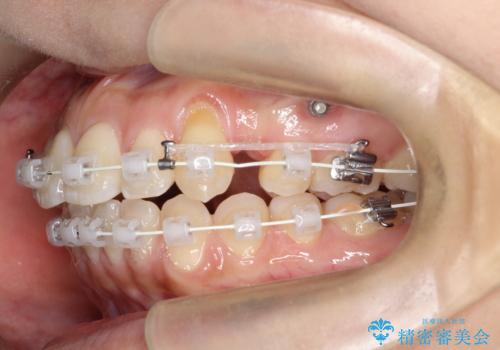

- 矯正装置

- 審美装置

小臼歯抜歯(上顎4番)して矯正治療を行なったことで、口元もスッキリしました。